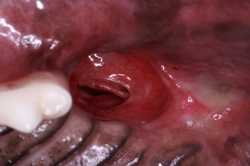

Extracción de restos radiculares en un gato

Otro problema muy común en perros es la presencia de fístulas oronasales. La fístula oronasal es una comunicación patológica de la cavidad oral con la cavidad nasal. Regularmente el paciente muestra una rinorrea unilateral que puede ser serosa, mucosa o sanguinolenta. Clínicamente se observa una pequeña abertura en la cavidad oral de la cual puede salir una secreción serosa, mucosa o sanguinolenta. La cavidad puede estar llena de pelo y detritus aunque algunas veces es poca su contaminación. La abertura es la punta de un iceberg, ya que la lesión ósea es regularmente mucho mayor. Se tiene la creencia de que puede cerrarse quirúrgicamente manejando solo los tejidos blandos pero eso es imposible. Se requiere un tratamiento quirúrgico de manejo combinado de tejidos duros y blandos para poder cerrar la fístula. Las fístulas oronasales pueden invadir el globo ocular, el seno maxilar y la cara, por lo que es muy importante realizar un diagnóstico temprano y la rápida resolución quirúrgica del defecto. El manejo de tejidos requiere realizar la extirpación total del tejido patológico de la cavidad nasal y de otras estructuras invadidas. Se requiere además de la ostectomía del tejido involucrado con una osteoplastia en donde los bordes del defecto óseo deben quedar sin ángulos cortantes y bien limados. Regularmente se requiere realizar colgajos de avance o de la forma mejor adaptable dependiendo del defecto. Otro problema poco común de origen congénito es la presencia de paladar hendido el cual puede ser ligero hasta muy severo. Estos casos regularmente se manejan como si fueran fístulas oronasales pero hay que tener cuidado con la elección en la decisión de preservar la vida de un espécimen en estas condiciones porque son pacientitos que nunca van a tener un desarrollo adecuado excepto de que el defecto sea lo suficientemente pequeño para cerrarlo en una sola intención.

Haz CLICK sobre la imagen para ver descripción.Cierre de fístula Oronasal

Fístula Oronasal en un caniche